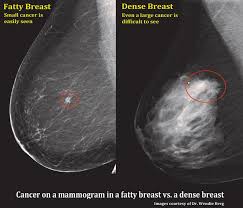

What Does Breast Cancer Look Like On An X Ray / X Ray Breast Cancer Mamary Tumor Stock Photo Picture And Royalty Free Image Image 53465851 : What does breast cancer look like?. Breast screening aims to detect breast cancer at an early stage, before symptoms or signs develop, such as a lump. It can be slightly uncomfortable, basically they xray your breast in simple terms. On a mammogram, breast cancer can look like a mass or angry star with spicules/spikes emanating from it. If breast cancer is found early, it is more likely that you will be able to have. Being called back does not mean you definitely have cancer.

Benefits Of 3 D Mammograms Last Over Time from www.breastcancer.org Genetic testing is the process of using medical tests to look for changes (mutations) in a person's genes or. What does breast cancer look like? Breast cancer is the uncontrollable growth of malignant cells in the breasts. Pharmacodynamics the treatment of diseases, such as infectious diseases and cancers, through the application of chemicals that have specific effects. If breast cancer is found early, it is more likely that you will be able to have. Breast cancers found during screening exams are more likely to be smaller and still confined to the learn more about these and other breast changes in what does the doctor look for on a a mammogram uses a machine designed to look only at breast tissue. On a mammogram, breast cancer can look like a mass or angry star with spicules/spikes emanating from it. The first mammogram may have.

Thoracic Manifestations Of Breast Cancer And Its Therapy Radiographics from pubs.rsna.org If breast cancer is found early, it is more likely that you will be able to have. What foods do you like? Breast screening aims to detect breast cancer at an early stage, before symptoms or signs develop, such as a lump. What does breast cancer look like on. What does lung cancer look like? Calcifications are calcium deposits within the breast tissue and they look like small white spots. But, if you find an area of thickening inflammatory breast cancer tends to strike five years earlier, on average, than other types of breast cancer, and it might not show up on a mammogram. What does breast cancer look like?